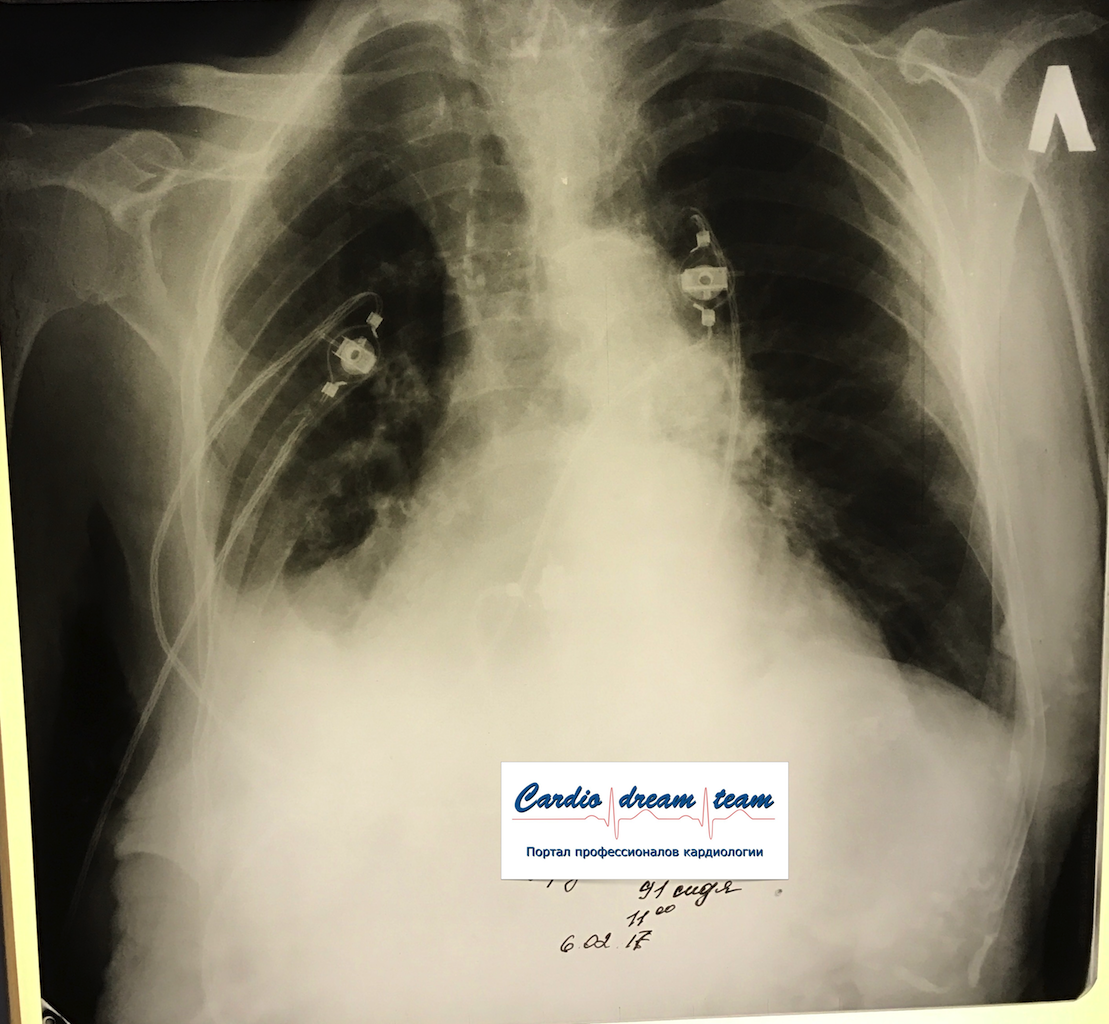

Гидроторакс. До и после пункции и лечения диуретиками.

Обсуждалось в Госпитале Ослабленных Сердец